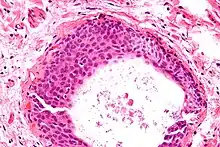

They appear as white/yellow cysts or nodules that can reach a size of 2 millimeters. They typically have elliptical nuclei with a long groove (along the major axis) – so-called "coffee bean" nuclei.

High magnification micrograph of a Brenner tumor showing the characteristic coffee bean nuclei which are also seen in Walthard cell rests. H&E stain.